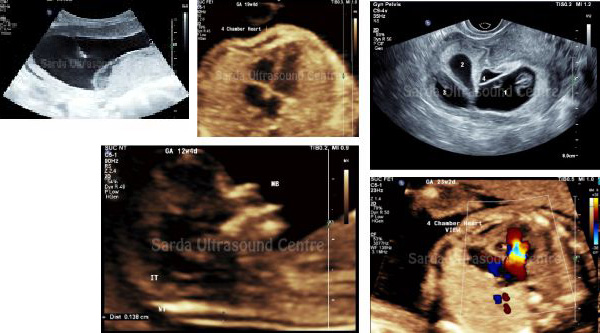

Our centre offers comprehensive fetal diagnostic services, including early pregnancy scans, NT scan, anomaly scans, growth monitoring, and Doppler studies to assess the well-being of the fetus; as well as Advanced and specialised scans like Fetal echo, Neurosonogram, 3D / 4D scans.

We are also recognised centre for invasive procedures like Amniocentesis and Chorionic Villous Sampling (CVS). We Emphasise on Patient counseling before and after the scan and procedures to make them understand the results better and relieve anxiety.